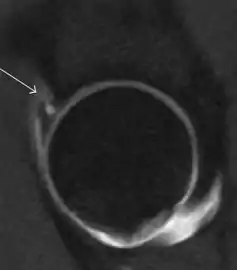

Intra-articular osseous causes of pain include several conditions: avascular necrosis (AVN), transient osteoporosis of the hip (TOH), tumors, and stress or insufficiency fractures. All these entities may present with a pattern of bone marrow edema characterized by decreased signal intensity on T1 weighted images and increased signal intensity on fluid sensitive sequences, such as fat saturated T2-weighted or STIR images. When there is no evidence of a focal lesion associated with the edema pattern, TOH is suspected. When a band of low intensity is seen inside the edematous area, the shape and length of this band become important. It is generally convex to the articular surface in the case of subchondral stress or insufficiency fractures, whereas it is concave, circumscribing all of the necrotic segment, in cases of AVN. When doubts do persist, gadolinium-enhanced MRI tends to show that the proximal portion beyond the band is enhanced in fractures but is not in AVN.[1]

MRI has been shown to have 100% sensitivity and specificity in prospective studies of occult hip fractures. These fractures were diagnosed by bone marrow edema and a low signal fracture line, mainly on T1 or T2 weighted images (Figure 10).[1]

Figure 10: